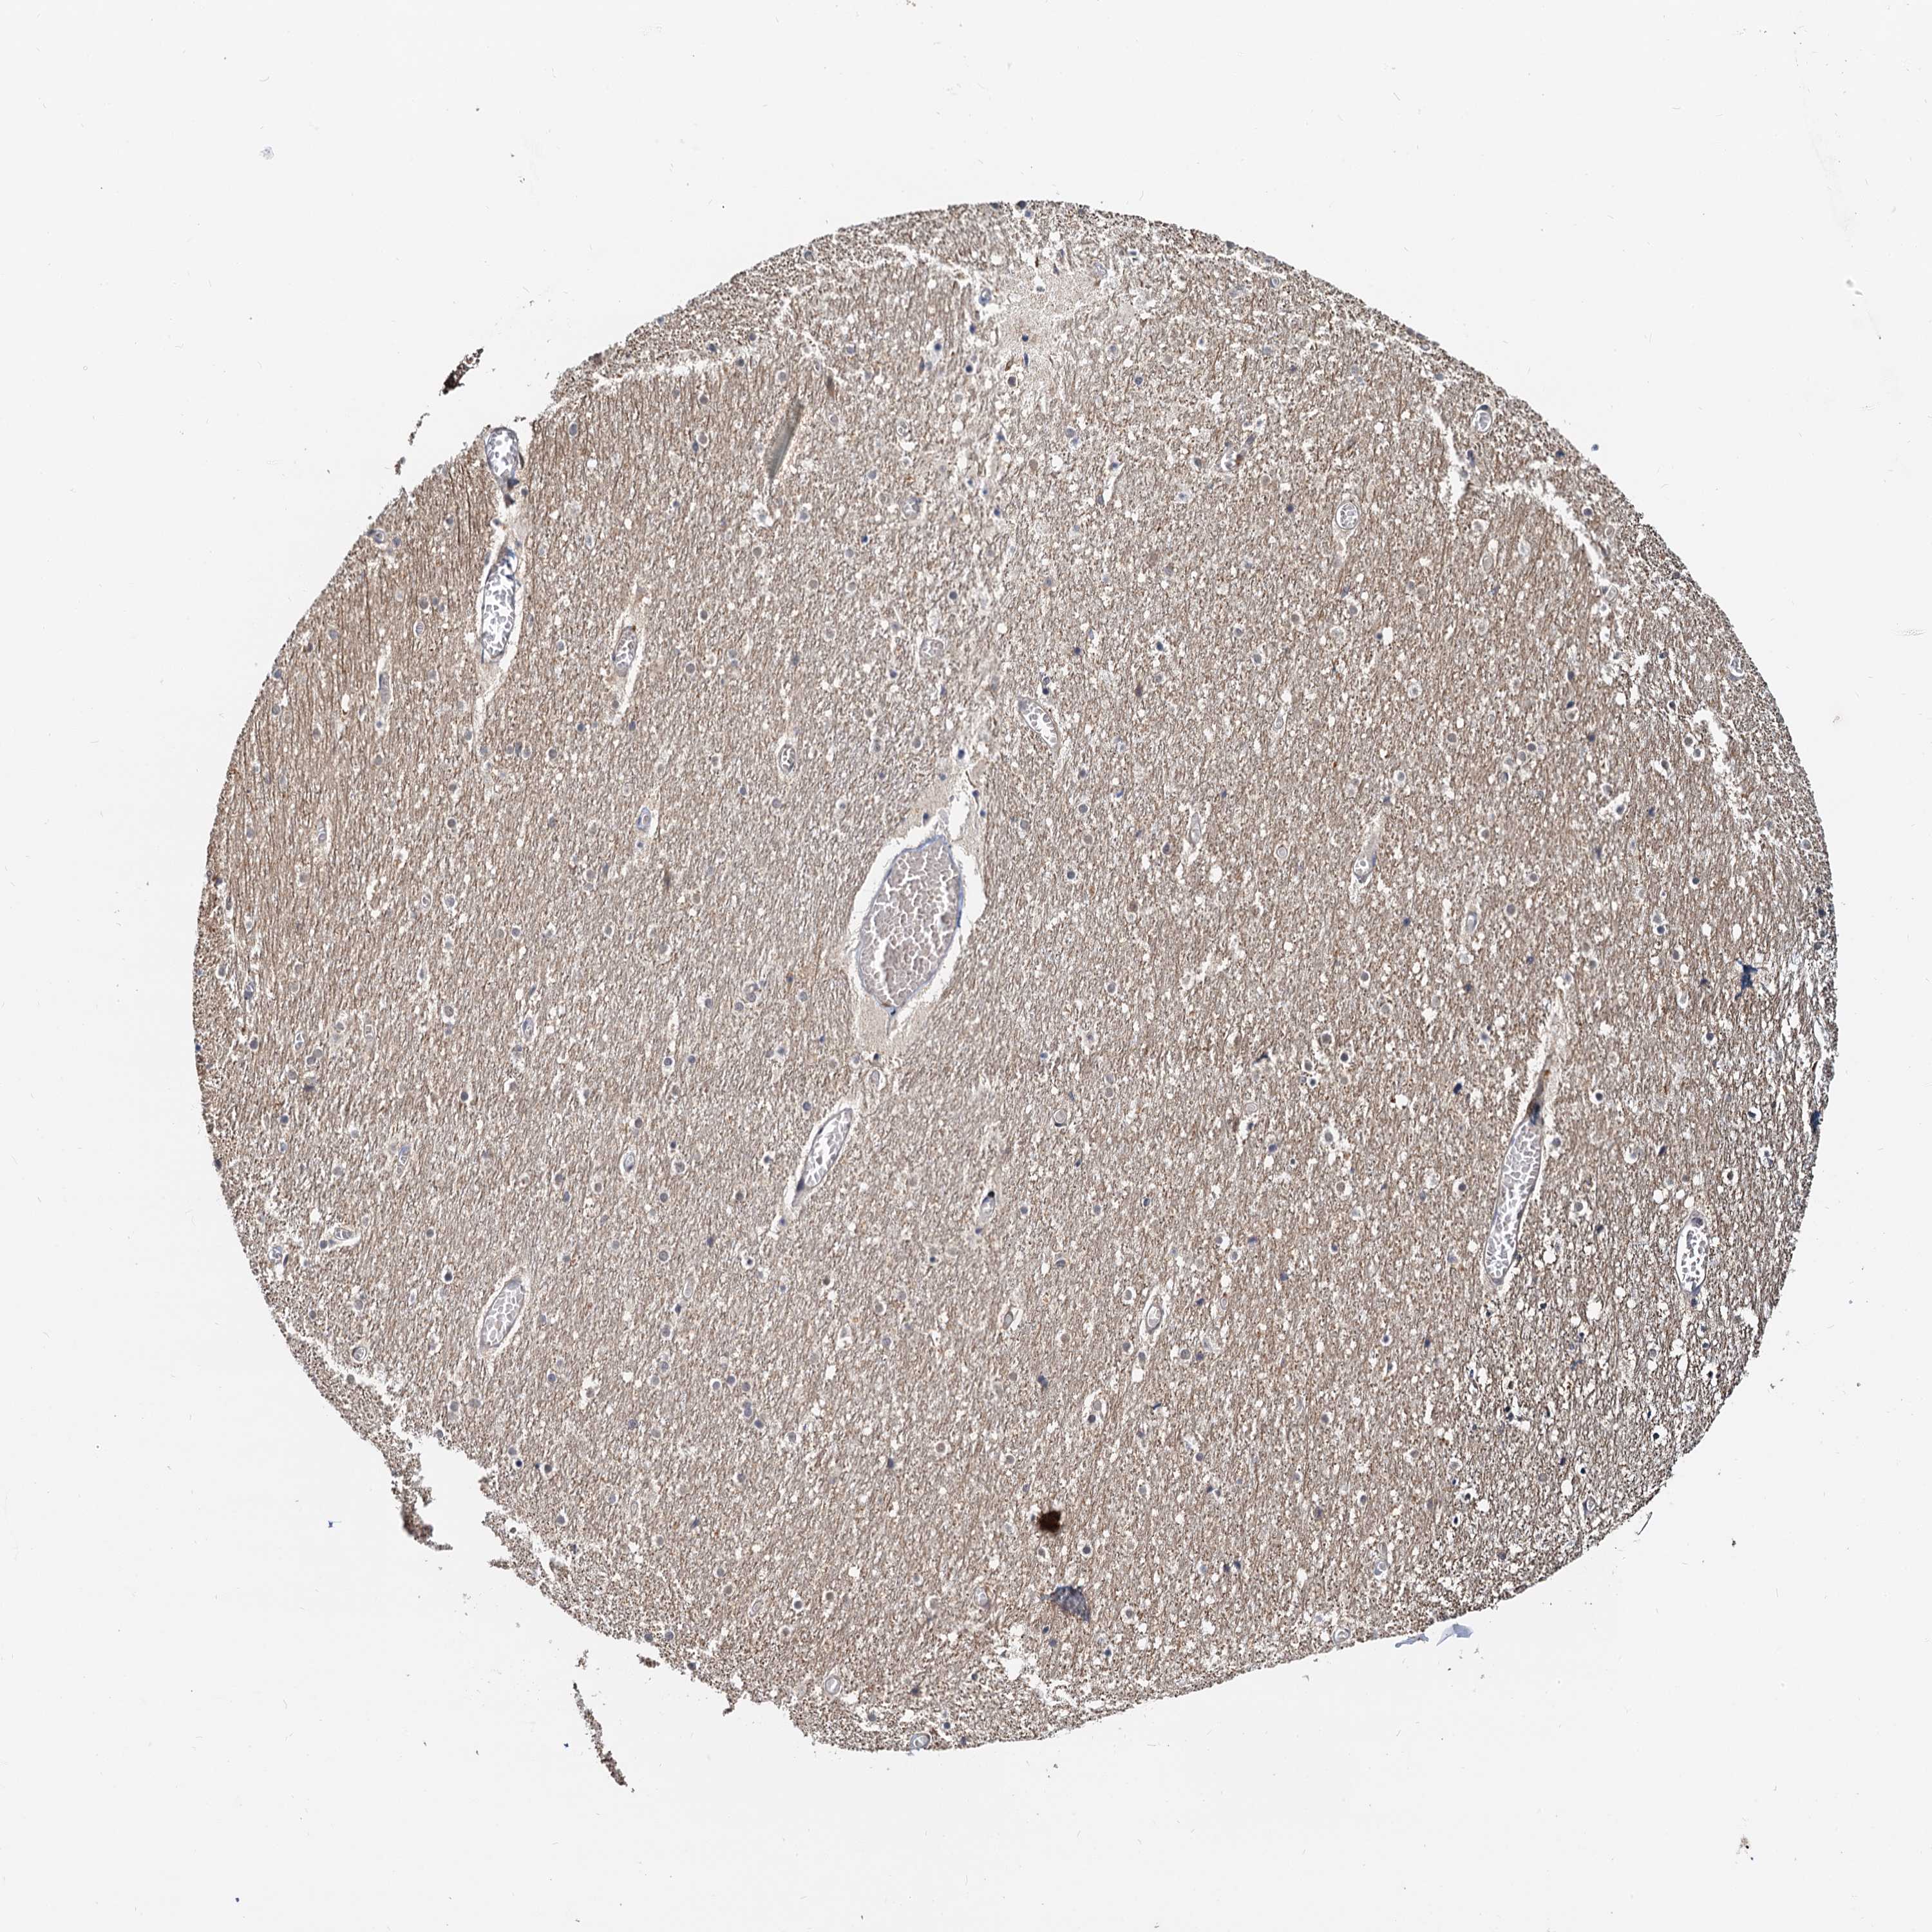

Antibody staining in the annotated cell types in the current human tissue is reported as not detected, low, medium, or high. This score is based on the staining intensity and fraction of stained cells.